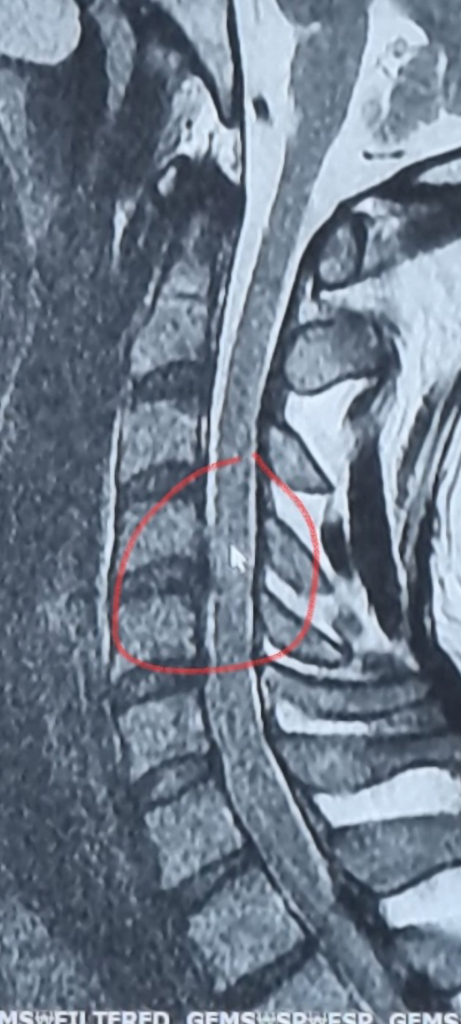

경추 후종인대 골화증 ct mri 사진좀 봐주세요...

척수병증이 MRI에서 보일려면 척수에 병변이 있어야 합니다, 그러니까 색이 변해야 하는거죠

현재는 그런 양상은 보이지 않고 표시한 부분에서 압박하는 양상만 보입니다

신경외과 교수님 말씀에 동의합니다